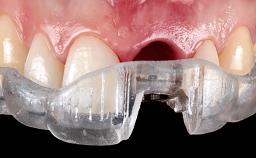

Immediate Replacement of Four Mandibular Anterior Teeth with a Conventionally Loaded Implant-Supported Fixed Dental Prosthesis

This case from German Gallucci, Adam Hamilton, and Teresa Chanting Sun details immediate placement with a conventional loading protocol (type 1C). It demonstrates a digital workflow combined with risk assessment to determine the best possible treatment approach for replacing mandibular anterior teeth.

Loading Protocol Early/Conventional

Interim prosthesis Tooth supported

Implant-supported provisional restoration Required, elevated esthetic and/or functional demands